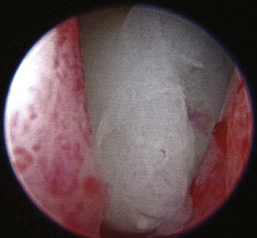

Aspergillus fumigatus is the most common canine fungal rhinitis.26 Chronic, unilateral mucopurulent to mucohemorrhagic nasal discharge is often reported. Serologic,3 CT, and MRI27 findings lack sensitivity and specificity, respectively, for reliable diagnosis of sinonasal aspergillosis. Rhinoscopic visualization and histopathologic evaluation are necessary for diagnosis confirmation. The classic fungal rhinitis lesion is a green-gray, whitish, necrotic plaque in the midcaudal nasal cavity. Regional turbinate reactive hyperplasia can be present, making the visual examination findings heterogeneous at best (Figures 19-31 through 19-33). The frontal sinuses should be examined in patients with suspected fungal rhinitis because treatment of all fungal mats is necessary for disease resolution. Sinusoscopy, sinusotomy, or both are often recommended to access and debride frontal sinus fungal mats and for antifungal instillation.28 Several treatment protocols have been described employing either single-agent sinonasal lavages or systemic antifungal therapy, depending on the fungus. We believe rhinoscopic debridement and flushing to remove fungal plaques improves the response to local treatment.

image

Figure 19-31 Canine nasal aspergillosis with mucus, hyperplasia, and ulceration.

Figure 19-32 Canine nasal aspergillosis with ulceration as the source of epistaxis.